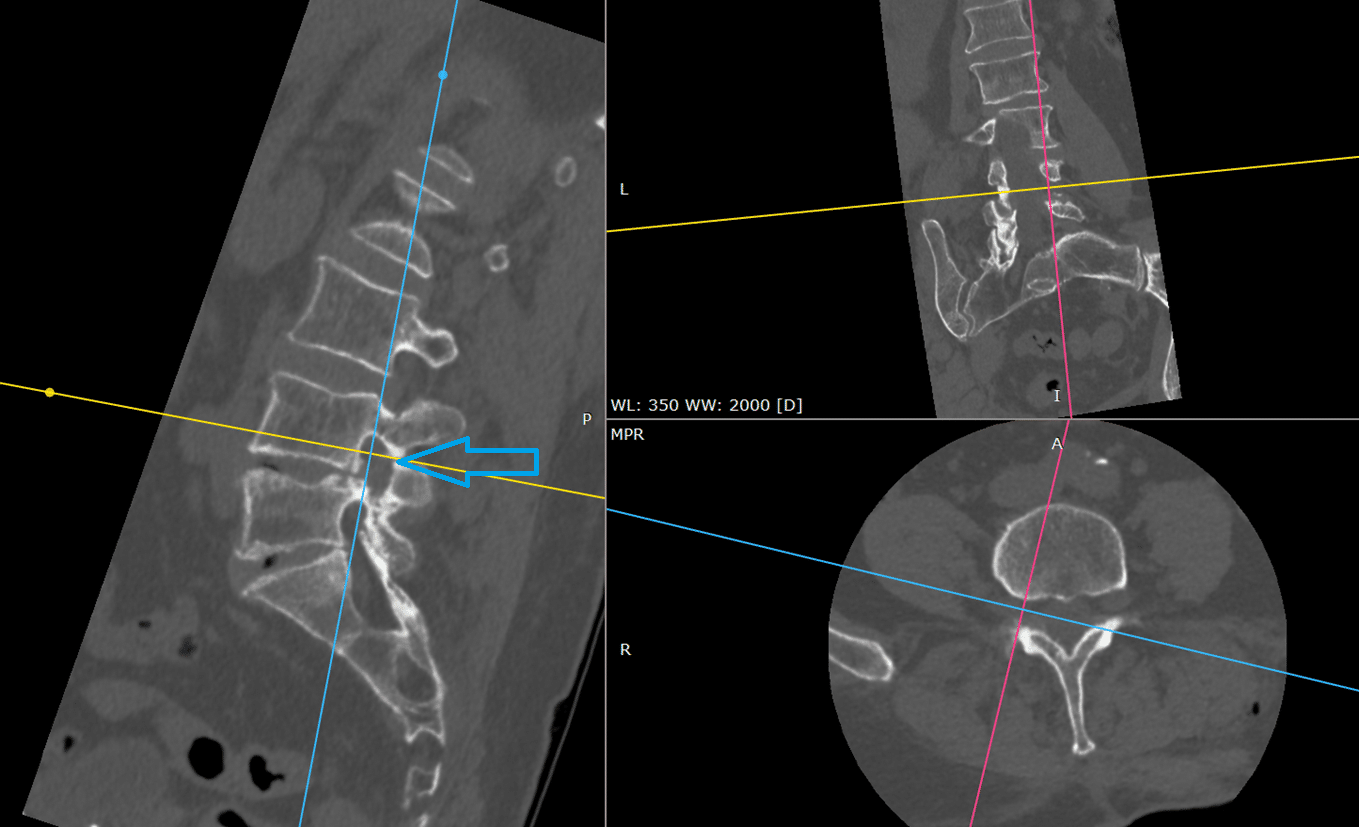

Obraz 2: TK Po Zabiegu

W badaniu tomografii komputerowej po zabiegu widoczne jest poszerzenie wymiarów kanału korzeniowego.

Obraz 3: Porównanie Otworów

W ocenie porównawczej otworów na poziomie segmentu L4/L5 potwierdziliśmy, że techniką endoskopową odtworzono wymiary otworu porównywalne do strony przeciwnej, która nie powodowała dolegliwości bólowych.